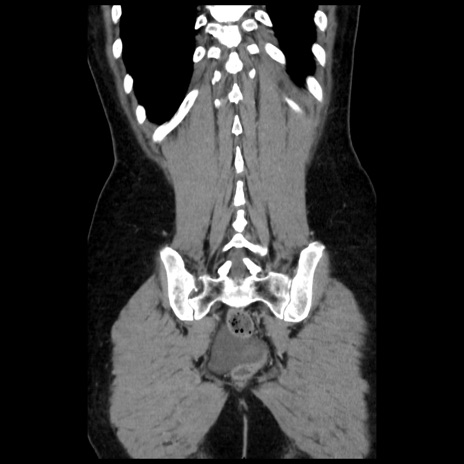

症例10(冠状断像)

【症例】 50歳代女性

【主訴】 腹痛

【現病歴】前日生レバーを食べた。今朝に排便あり。 昼前に突然発症の腹痛を生じ、当院救急外来を受診した。

【既往歴】 子宮筋腫にてで子宮全摘後

【身体所見】 意識清明、腹部:平坦、軟、下腹部やや左を中心に圧痛・反跳痛あり、筋性防御あり

【データ】WBC 7800、CRP 0.07